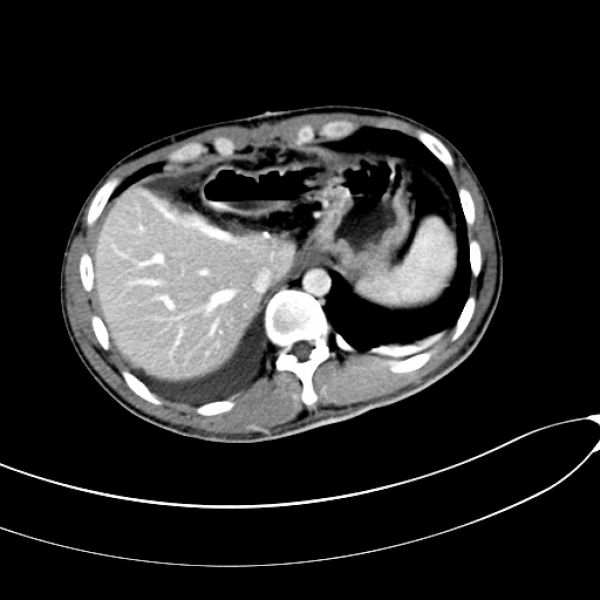

10月20日,创伤骨科收治了一位特殊的病人。患者黄某,28岁,因“高空坠落致右大腿肿痛、活动受限8小时”求诊。入院后检查发现,小伙子不仅多处骨折,还伴随内脏受损:左肝中央型挫裂伤。

术前CT